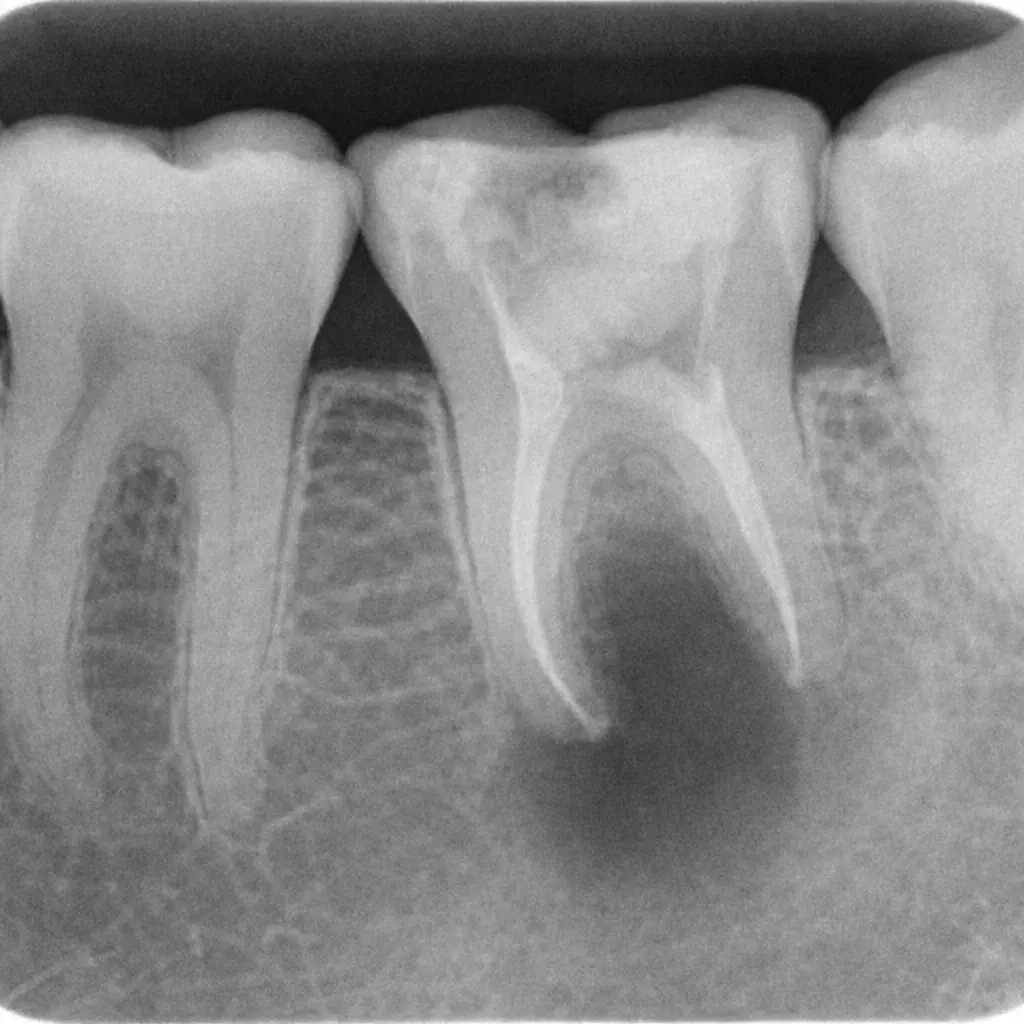

Infection exits through the root tip into the surrounding bone. A pus pocket forms. On X-ray, this shows as a dark shadow (periapical radiolucency) around the root tip. A gum fistula may appear.

On an X-ray: A tooth abscess appears as a dark shadow at the root tip — this dark area is destroyed bone. The larger the shadow, the longer the infection has been active. At our Gurgaon clinics, we use digital X-rays to measure bone involvement accurately. See how this affects treatment planning.

Periapical X-Ray or CBCT

A targeted X-ray shows if infection has spread beyond the root tip. We use a strict CBCT imaging protocol for complex cases — giving us precise, 3D data to plan treatment accurately.